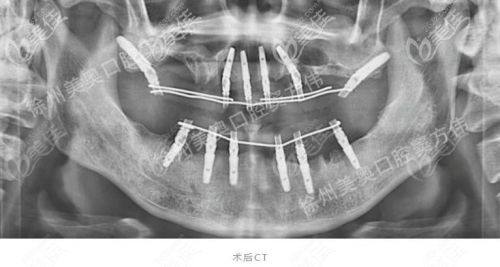

口腔种植修复:能够开展口腔种植修复相关项目,根据患者口腔条件定制合适的种植方案,改善牙齿缺失问题,修复咀嚼功能与美观度。

“我因为意外磕掉了上前牙,一直不敢出门见人,经朋友介绍找到阿依加玛丽医生做种植牙修复,她先帮我做了全方面的口腔检查,制定了个性化的种植方案,整个手术过程特别顺利,术后修复也特别快,现在牙齿看起来和真牙一模一样,终于能自信地笑了。”